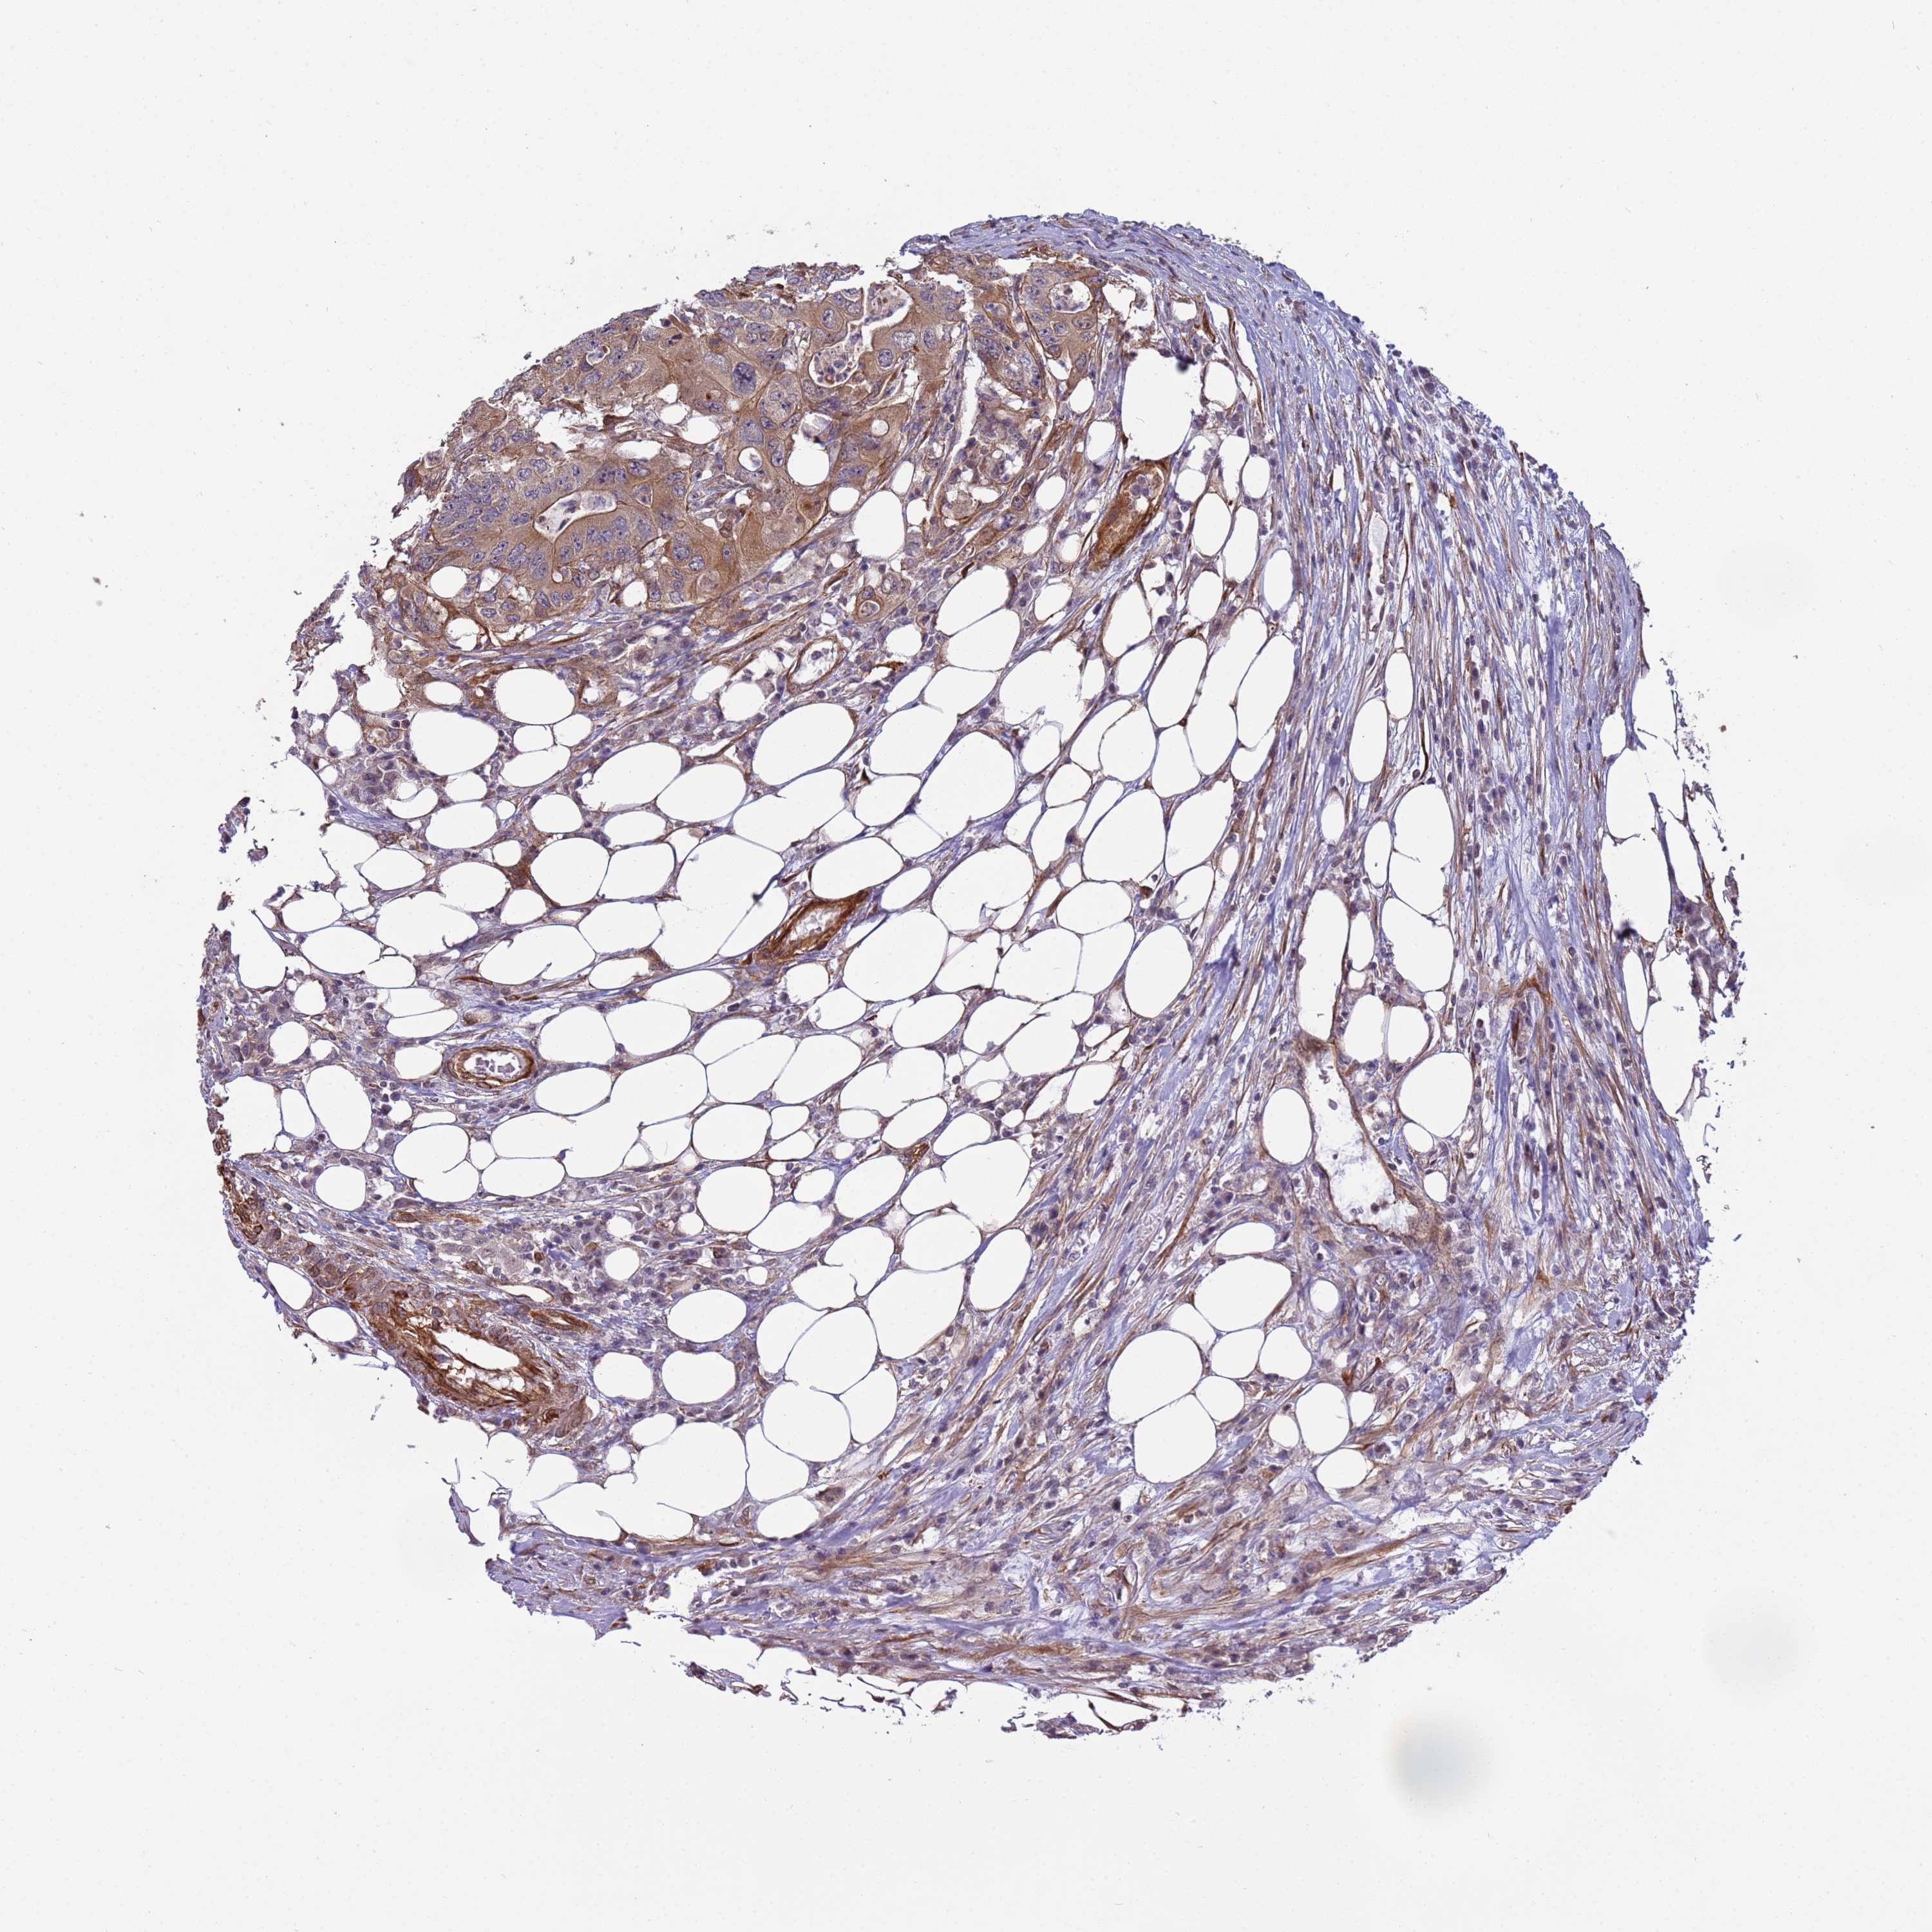

CANCER COLORECTAL CANCER Show tissue menu

Colorectal cancer

Human cancer

Colon adenocarcinoma